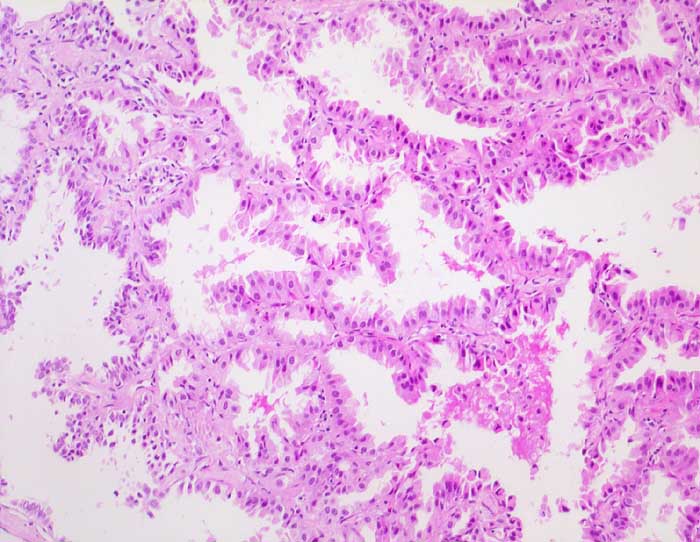

Das Bronchioloalveoläre Karzinom stellt eine Variante des Adenokarzinoms dar. Die Tumorzellen wachsen per Definition auf dem intakten Alveolargerüst, ohne das Stroma zu infiltrieren. Nicht selten zeigen Ausläufer gewöhnlicher Adenokarzinome ein bronchioloalveoläres Wachstumsmuster. Bei diesen Tumoren handelt es sich jedoch nicht um echte bronchioloalveoläre Karzinome. Da eine Invasion zytologisch nicht ausgeschlossen werden kann, ist die zytologische Diagnose eines bronchioloalveolären Karzinoms nicht eindeutig möglich. Die Karzinomzellen schilfern in kleinen Gruppen oder dreidimensionalen Verbänden in die Alveolarlichtungen ab. Multiple kleine papilliforme Zellverbände, die mit Creolakörperchen verwechselt werden können, sind typisch. Im Sputum erscheinen die Tumorzellen kleiner als die der üblichen Adenokarzinome. Die Kerne liegen exzentrisch, sind rund und glatt begrenzt, das Chromatin ist blass. Kernkerben und Pseudoinklusionen sind möglich, Nukleolen sind unauffällig. Das reichlich vorhandene Zytoplasma färbt sich blass eosinophil bis blass zyanophil. Beim muzinösen Subtyp ist es unterschiedlich vakuolisiert. Aufgrund der geringen Kernatypien ist die Unterscheidung von einer Becherzellhyperplasie bisweilen schwierig. Pseudoepitheliale Verbände aktivierter Makrophagen und hyperplastische Alveolarzellen, wie sie bei Lungeninfarkten oder Lungenfibrosen vorkommen verschwinden im Gegensatz zum ähnlich aussehenden bronchioloalveolären Karzinom in wiederholten Sputumkontrollen.

Der erste Fall zeigt ein muzinöses, der zweite Fall ein nicht muzinöses bronchioloalveoläres Karzinom.